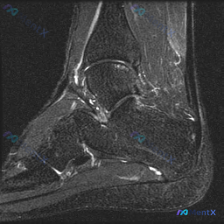

刚整理完这份膝关节MRI的读片思路,这个病例其实挺有代表性,很容易犯锚定错误,分享给大家一起看看。 病例基本影像信息 本次提供的是膝关节MRI矢状位T2加权图像,具体影像学发现如下: 1. 骨骼结构:股骨远端髁前部及滑车无明显骨折,胫骨平台关节面完整无塌陷,髌骨结构未见明显异常;股骨远端周围皮下软组...